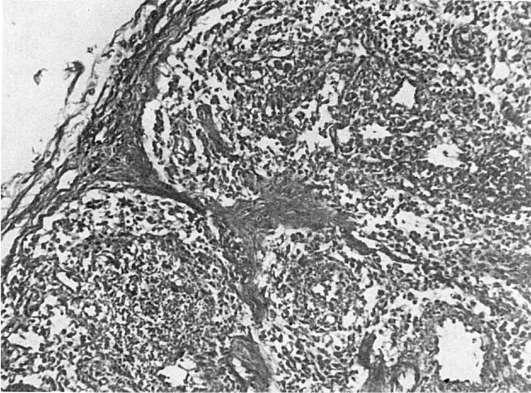

Патологическая анатомия. Происходят изменения лимфатических узлов, характерные поражения ЦНС и изменения, типичные для оппортунистических инфекций и опухолей. Фолликулярная гиперплазия лимфатических узлов сменяется полным истощением их лимфоидной ткани (рис. 253). Лимфатические узлырезко уменьшаются, определяются с трудом. Поражение ЦНС представлено ВИЧ-энцефаломиелитом, при этом основные изменения находят главным образом в белом веществе и подкорковых узлах мозга. При микроскопическом исследовании находят микроглиальные узелки, многоядерные симпласты, в которых удается обнаружить частицы ВИЧ. В боковых и задних столбах спинного мозга определяются очаги размягчения и вакуолизация белого вещества. Благодаря демиелинизации белое вещество приобретает сероватый оттенок. Для оппортунистических инфекций при СПИДе характерно тяжелое рецидивирующее течение, часто с генерализацией процесса и устойчивостью к проводимой терапии. Оппортунистические инфекции могут вызываться простейшими (пневмоцисты, токсоплазмы, криптоспоридии), грибами

(рода Candida, криптококки), вирусами (цитомегаловирусы, герпетические вирусы, некоторые вирусы медленных инфекций), бактериями(Mycobacterium avium intracellulare, легионелла, сальмонелла). Одна из самых частых и характерных инфекций при СПИДе вызывается пневмоцистами. Она приводит к развитию тяжелой пневмонии с образованием в альвеолах большого количества пенистых эозинофильных масс, в ко-

Рис.

торых выявляются пневмоцисты. Довольно часто возникает и токсоплазменная инфекция, при которой находят энцефалит; для него характерны фокусы некроза и абсцедирования. При криптоспоридиозе поражается кишечник, развиваются энтериты и колиты, проявляющиеся длительной профузной диареей. Среди поражений грибами часто отмечается кандидоз с вовлечением пищевода, трахеи, бронхов, легких, а также криптококков, склонный к диссеминации процесса. Из вирусных инфекций наиболее типична цитомегаловирусная с развитием ринита, пневмонита, колита, энцефалита. Герпетической инфекции свойственно длительное поражение слизистых оболочек и кожи. Среди бактериальных инфекций наиболее характерна атипичная микобактериальная инфекция Mycobacteria avium intracellulare, которая приводит к развитию диссеминированного процесса с поражением лимфатических узлов и внутренних органов.